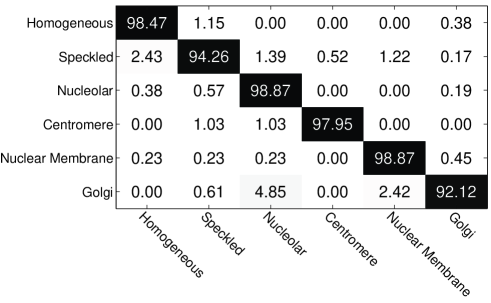

In addition, the confusion matrix of the best CNN (trained with the rotation angle step of ) is shown in Fig. 10. The overall classification performance is very promising. The staining patterns Nucleolar and Nuclear Membrane obtain the highest classification accuracy (both %), which means that they are well separated from the others. The maximum misclassification rate (%) happens to Golgi cells. They are easy to be misclassified as Nucleolar cells, because both patterns consist of a few large dots within the cells (see misclassification examples in Fig. 11). Also, Golgi can be confused with Nuclear Membrane. This may be because when the large dots within Golgi cells are at the edge, they will look like the Nuclear Membrane cells having ring-like edges. In addition, the Speckled cells are easy to be misclassified as Homogeneous cells, probably because the densely distributed speckles are the main signatures for both patterns. Misclassification examples of these staining patterns are shown in Fig. 11.